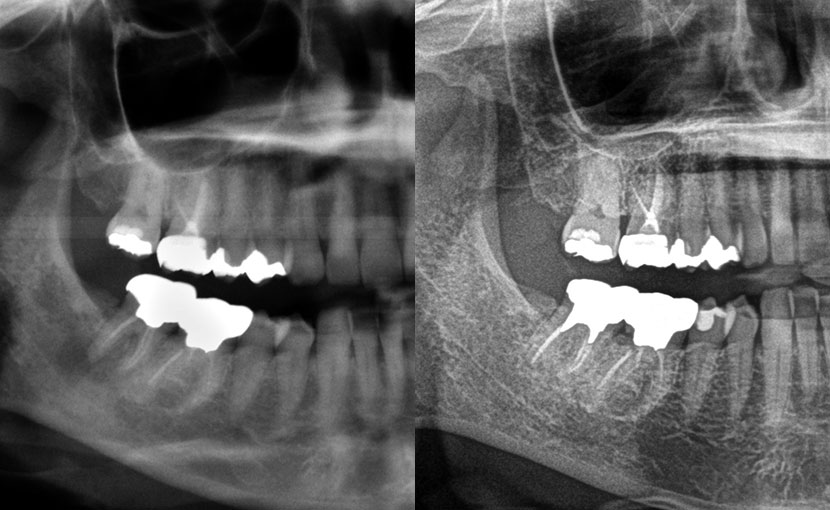

術直後レントゲン写真

2次元的デンタルレントゲン写真から、根っこの先にMTAと呼ばれる薬が充填(逆根充)されていることが確認できます。

術後10年後レントゲン写真

根っこの先の透過像が消失しているのが確認できます。